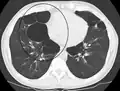

A realização de uma radiografia ao tórax e de um hemograma permitem excluir outras condições no momento do diagnóstico.[69] Os sinais característicos da DPOC observáveis em radiografia são pulmões sobre-expandidos, diafragma achatado e espaço retroesternal aumentado. Ao mesmo tempo, a radiografia permite excluir outras doenças pulmonares, como pneumonia, edema pulmonar ou pneumotórax.[70] Uma tomografia axial computorizada ao tórax permite mostrar a distribuição do enfisema pelos pulmões e pode ajudar a excluir outras doenças pulmonares.[18] No entanto, a não ser nos casos em que se planeie a realização de uma cirurgia, esta distribuição raramente influencia o tratamento.[18] Pode ainda ser realizada uma gasometria arterial para determinar a necessidade de oxigénio suplementar. Este exame é recomendado em pessoas com VEF1 inferior a 35% do previsto, com saturação periférica de oxigénio inferior a 92% e pessoas com sintomas de insuficiência cardíaca congestiva.[17] Em regiões do mundo onde é comum a deficiência de alfa-1 antitripsina, as pessoas com DPOC devem considerar a realização deste exame, sobretudo aquelas com idade inferior a 45 anos e em que o enfisema afeta a parte inferior dos pulmões.[17]

Enfisema muito grave com cancro do pulmão à esquerda